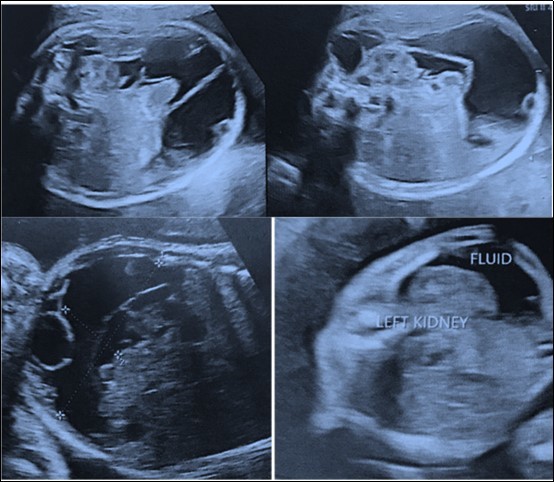

34 year old G2P1001 was referred to our institute at 21weeks period of gestation for a fetal abdominal cystic mass for further evaluation and management. At referral, she had an anomaly scan reporting a left sided retroperitoneal collection of 3x2 centimeters with septations surrounding the kidney and extending up to left pelvis suggestive of lymphocoele in the fetus. In second trimester anomaly scan nuchal fold thickness was normal, there were no markers suggestive of aneuploidy and no other malformation was seen. In follow-up scans, there was increase in size of the collection upto 8x6 cm at term which also shown a subcutaneous component of around 5x4 cm along the left fetal torso in the lumbar region (Figure 2a). Growth parameters were normal and amniotic fluid was adequate. She was hypothyroid on treatment and developed gestational diabetes at 32weeks period of gestation which was managed with medical nutrition therapy. Her first child was born by cesarean section and had no congenital malformation. Index pregnancy was terminated by an elective cesarean section at term as she was not willing for vaginal birth after caesarean. Male baby of 3.4kg was born with good apgar score. He had a left sided lumbar cystic swelling of 5x6cm, reducible inguinal hernia and undescended testes on the left side. Postnatal echocardiography was normal and postnatal USG shown similar features of the cyst. Baby was active, euthermic, euglycemic, passed urine and stool and was well accepting feeds hence discharged at day 3 of life. He was conservatively followed and at 6 months postnatal visit, size of the lumbar swelling was clinically decreased in size and infant had age appropriate milestones. Ultrasonography (Figure 2b) and CECT scan at one year of age was suggestive of large cystic lesion in the abdomen and pelvis (13*6*12 cm) with extension into postero lateral subcutaneous planes of abdominal wall through a defect in the left oblique muscle. Rest of the abdominal organs and large vessels were normal and there was no ascites or lymphadenopathy. However child is doing well at one year of age without any clinical obvious increase in the size of lumbar swelling.

Figure 2a.Images of Ultrasonography at second trimester of pregnancy